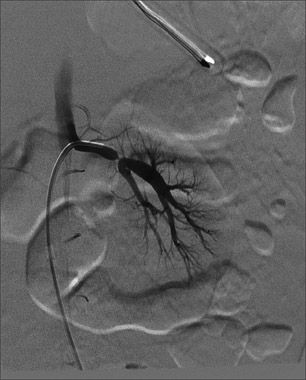

A 3-year-old boy with elevated blood pressure was brought in for vague abdominal pain. A hypertension evaluation revealed no definite abnormality. This angiogram shows a thread-like appearance of the left main renal artery, just proximal to the bifurcation, confirming a diagnosis of renal artery stenosis. Repeated blood pressure measurements confirmed that the boy had stage 2 hypertension.